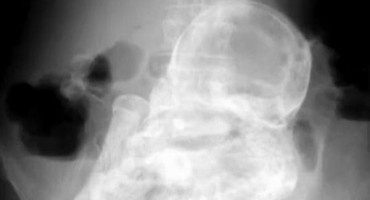

Kada je 82-godišnja žena došla na pregled zbog bolova u trbuhu, liječnici u bolnici u Bogoti otkrili su rijedak slučaj litopediona, odnosno okamenjenog djeteta, javlja AP.Zbog čega je…